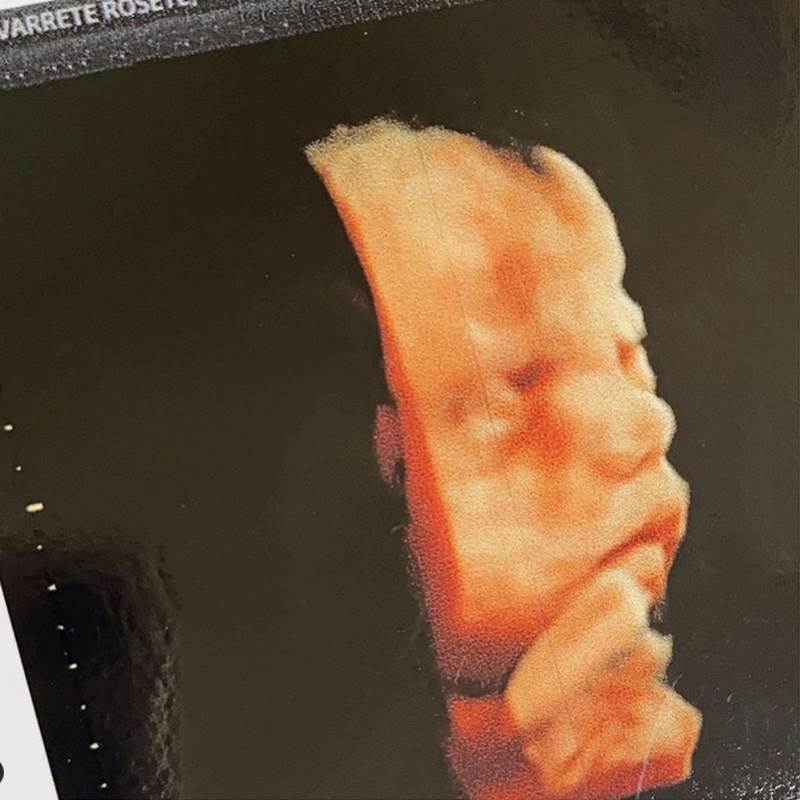

A pocas semanas de dar a luz, Ximena Navarrete compartió una tierna imagen de su más reciente ultrasonido en el que se aprecia la carita de su bebé. Ya en la recta final de su embarazo, la modelo tapatía tiene encandilados a sus seguidores ya que presume constantemente detalles de su dulce espera y así lo demostró con una hermosa foto de la ecografía 3D que recibió en su reciente visita al ginecólogo.

“Mi cosita bella … te amo bebé”, escribió la exreina de belleza junto a la bella postal de su hija, la cual procreó junto a esposo Juan Carlos Valladares y quien nacerá este diciembre próximo. Navarrete espera con mucha ilusión a su retoño, pues para quedar embarazada se sometió a un tratamiento de fertilidad debido a que tenía una baja reserva ovárica, según comentó en un LIVE the Instagram.